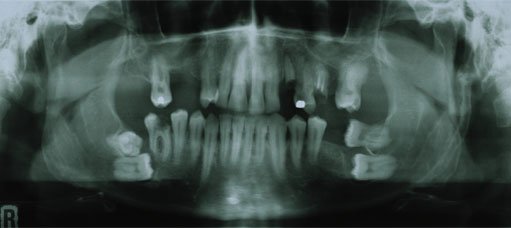

Die Tatsache, dass ein Weisheitszahn im üblichen Alter noch nicht durchgebrochen ist, stellt noch keinen Grund zur Entfernung dar. Die Beurteilung erfolgt deshalb individuell mit den entsprechenden klinischen und röntgenologischen Befunden (Panoramaschichtaufnahme).

Die häufigsten Gründe für die Entfernung der Weisheitszähne sind nachfolgend aufgeführt.

Weisheitszähne, die teilweise oder vollständig unter dem Zahnfleisch liegen und nicht in die Zahnreihe eintreten, können